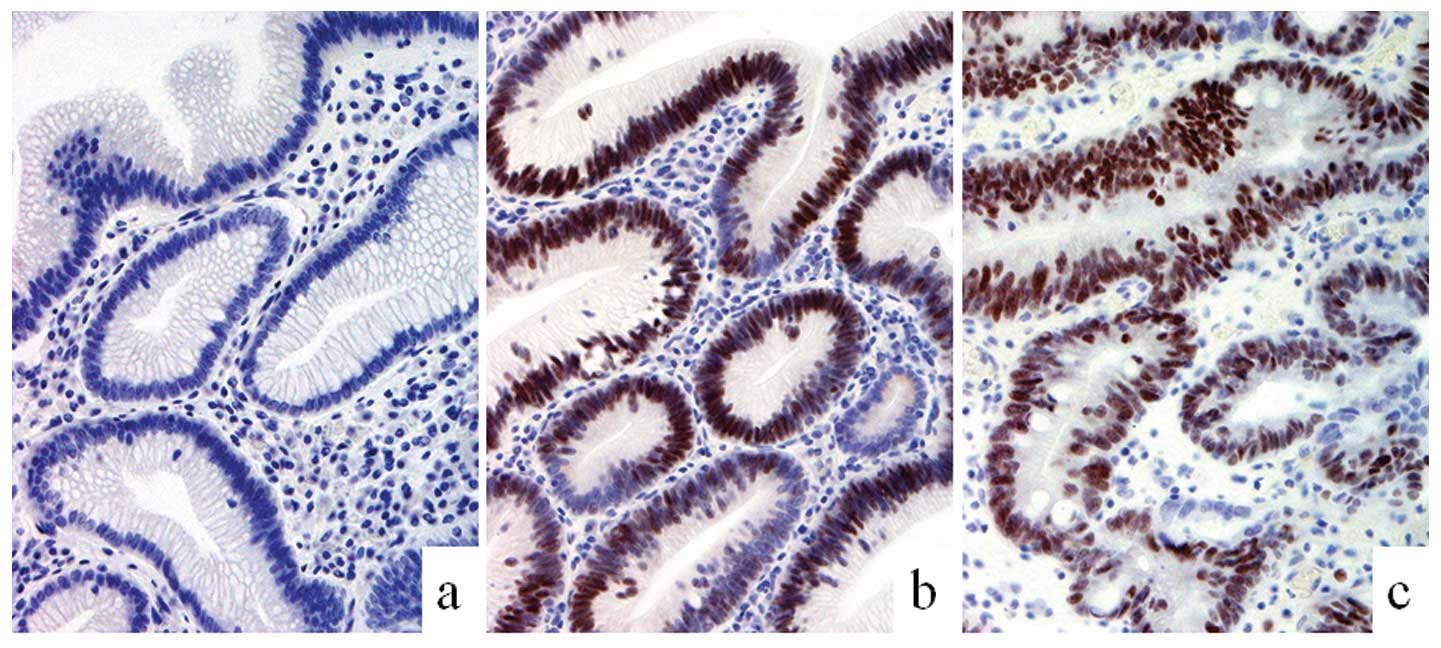

cells of the intestinal epithelium was found in the dysplastic and

carcinomatous components of all cases with the exception of one

case (Fig. 4). The tight junction